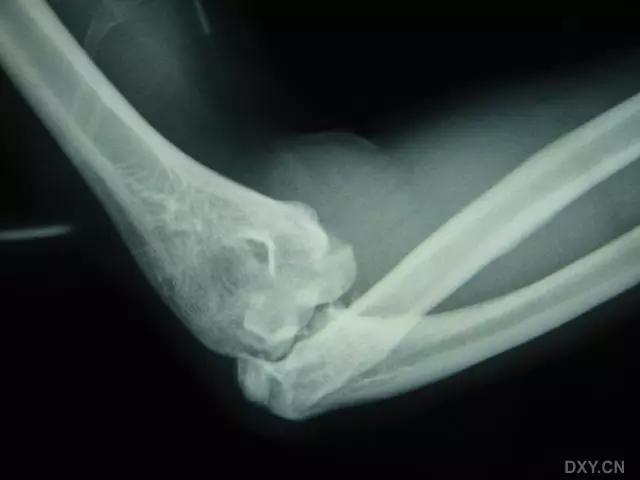

6. Hahn-steinthal 骨折

全肱骨小头骨折,为一种少见的关节内骨折,多见于成年人。常由于跌倒时手过度伸直或在屈肘时因桡骨小头撞击肱骨小头,并同时有外翻力存在时发病,亦可伴有滑车骨折与内侧副韧带的撕裂。X 线表现为全肱骨头骨折,向上移位。

Hahn-steinthal 骨折 X 片(来源:Hahn-Steinthal fracture: a case report.BioMed central Cases Journal20081:239)

Hahn-steinthal 骨折 CT 片(来源:Hahn-Steinthal fracture: a case report.BioMed central Cases Journal20081:239)